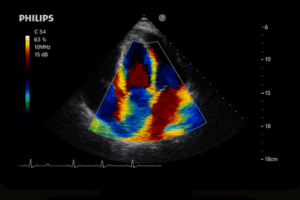

- modernes Rehazentrum mit neuester technischer Ausstattung

- präventivmedizinische Untersuchungen mit Auswertung und Beratungsgespräch einschließlich Ultraschalluntersuchungen

- Erfahrung in der kardiologischen Diagnostik

- Sonographiekenntnisse in den Bereichen Abdomen, Schilddrüse, Karotiden und Echokardiografie